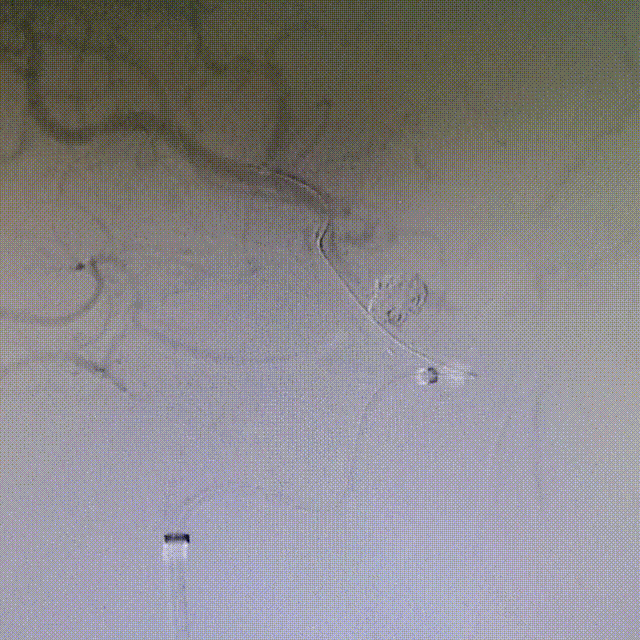

顶住Evolve支架钢丝,退XT-27支架导管,支架远端定位在Atlas的远端Mark以近2mm,并顺利打开。

由于血管平直,继续顶住Evolve支架钢丝,退XT-27支架导管,当支架释放至颈内C7段时,整体推支架系统增张,让瘤颈口处的支架充分贴壁,将内翻的钢梁压到血管壁上。

Evolve支架尾端减张释放,当支架尾端自行弹开后,将XT-27沿支架钢丝从支架内送回到远端,在将支架钢丝从XT-27中撤出体外。留XT-27支架导管在远端,为下一步导丝按摩提供通路。

术后即刻工作位造影显示,支架全程打开形态良好,充分贴壁。